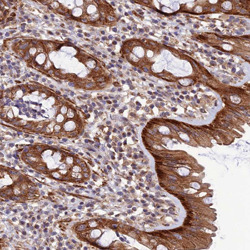

- Main image

- Immunohistochemical staining of human rectum with LEKR1 polyclonal antibody (Cat # PAB27520) shows strong cytoplasmic positivity in glandular cells at 1:1000-1:2500 dilution.

- Validation comment

- Immunohistochemistry (Formalin/PFA-fixed paraffin-embedded sections)